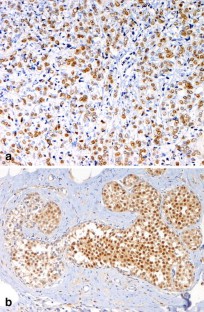

Androgens and androgen receptors (AR) are involved in the pathogenesis of breast cancer. Epidemiological studies have shown a significant association between the risk of breast cancer and androgens. However, the functional role and clinical value of AR expression in breast carcinoma have still not been clearly defined. The present study was set up to investigate the prevalence of ARs in a series of consecutive invasive breast carcinomas (IBCs) and to evaluate the patterns of AR phenotypes in a series of selected invasive lobular carcinomas (ILCs). Among the 250 consecutive IBCs (consisting of 212 ductal and 38 lobular neoplasms), AR immunoreactivity was observed in 151/250 (60.4%) cases, being expressed in 118/212 (56%) ductal and 33/38 (87%) lobular carcinomas (a statistically significant difference, χ2=11.82). AR expression was frequently associated with ER (65.2%, χ2=14.33) and PR positivity (66.9%, χ2=7.36). Most AR positive cases showed a low proliferative index (63.7%) and a low or intermediate histological grade (G1–G2, 63.9%). Among the 80 selected ILCs, AR expression was observed in 64/80 (80%) cases. Our results confirm that ARs are expressed in most breast cancers. Moreover, we demonstrated that AR positivity is particularly marked in lobular neoplasms. In addition, AR positive carcinomas are frequently characterized by a low or intermediate grade, a low proliferative index and ER and/or PR co-expression.

Fig. 1

Fig. 2

Fig. 3